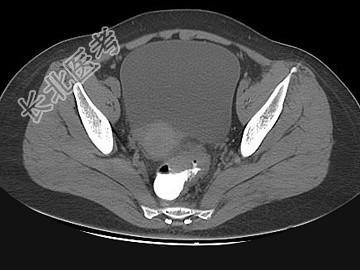

- 单项选择题女,67岁, 排便习惯改变,血便3月入院, CT检查如图所示,下列说法错误的是 ( )

A、直肠肠腔局限性增厚

B、其表面欠光整,边界欠清晰

C、可做直肠指检及活检以确定病变性质

D、此为直肠息肉

E、此为直肠癌